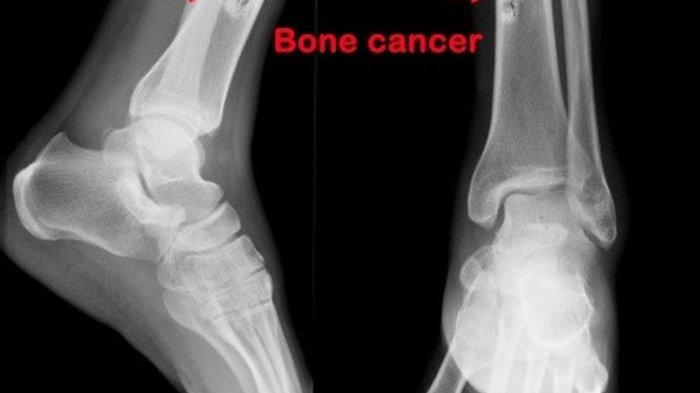

X-ray dapat dilakukan oleh seorang profesional medis untuk memeriksa penyebab yang mendasari nyeri tulang.

"Jika X-ray menunjukkan area abnormal, Anda akan dirujuk ke ahli bedah ortopedi," kata NHS.

Sinar-X adalah alat yang efektif untuk mendeteksi kerusakan tulang yang disebabkan oleh kanker.